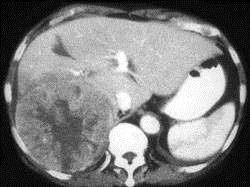

男,69岁,肝区疼痛,消瘦乏力三月余,CT检查如图,请作出最可能诊断 ( )A、肝转移瘤B、巨块型肝癌C、肝脓肿D、肝血管瘤E、肝囊肿

问题 男,69岁,肝区疼痛,消瘦乏力三月余,CT检查如图,请作出最可能诊断 ( )

选项 A、肝转移瘤 B、巨块型肝癌 C、肝脓肿 D、肝血管瘤 E、肝囊肿

答案 B